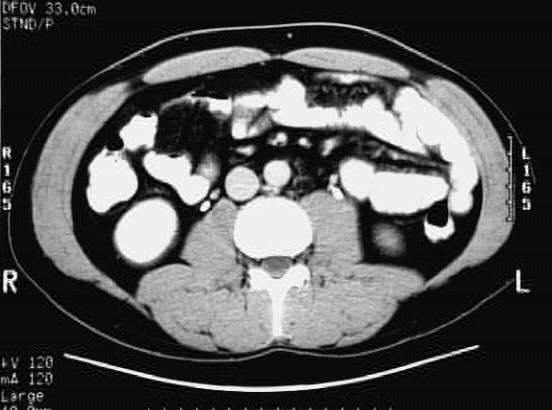

Abdomen- Abdomen Cross 7 :